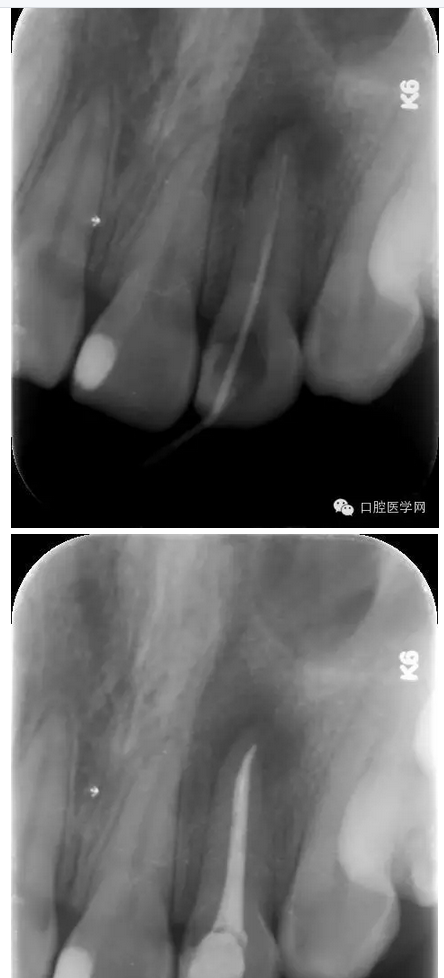

治療:第一次:去舊充填體,去腐質(zhì),GG鉆去除牙膠充填體,疏通根管,測(cè)量工作長短,H銼與K銼去除剩余牙膠,雙氧水和鹽水大量沖洗,機(jī)擴(kuò)至S1,超聲蕩洗,激光行根管消毒,封CP球。

第二次:復(fù)診無不適,回去后疼痛即刻解除。叩診無不適。無松動(dòng)。處置:去暫封,見根管內(nèi)無滲出,機(jī)擴(kuò)至F2,雙氧水和鹽水大量沖洗,超聲蕩洗,激光蕩洗加消毒,干燥,封氫氧化鈣。

第三次:復(fù)診無不適。叩診無不適,無松動(dòng)。處置:去除暫封物,鹽水沖洗,試尖,牙膠尖+AHplus糊劑冷測(cè)壓充填,玻璃離子體充填。